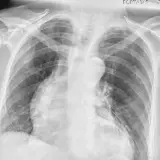

Over 2,100 interactive radiology cases, curated by radiologists for your level of training. Scroll, window, and view cases full screen — just like on PACS. Click linked findings in each writeup to jump straight to them on the image. Cases include sample reports, a focused discussion section, original illustrations, and videos.

PACSで期待されるツールを完備した完全インタラクティブな症例 — スクロール、ウィンドウ調整、ズーム、パン、計測、ROI、フルスクリーンモード。

重要な所見を症例画像上に直接ハイライトする豊富なアノテーション。症例解説内のリンクされた所見をクリックすると、スキャン上の正確な位置へジャンプできます。

アノテーション付きの画像所見とイラストで効率的に学習